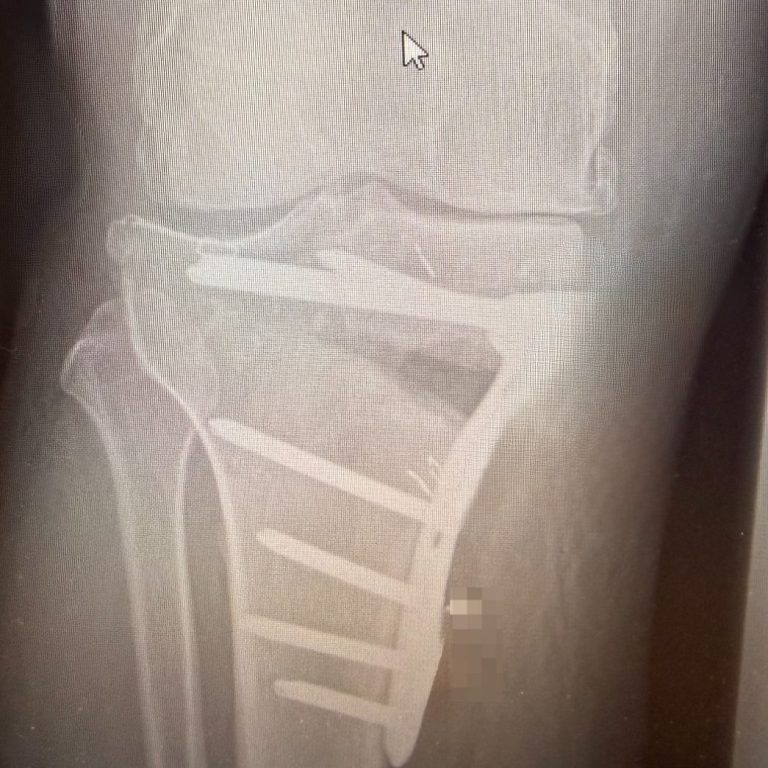

Metallentfernung

bei Jungen Patienten und-/oder störenden Implantaten kann eine Entfernung der Platten oder Schrauben sinnvoll sein